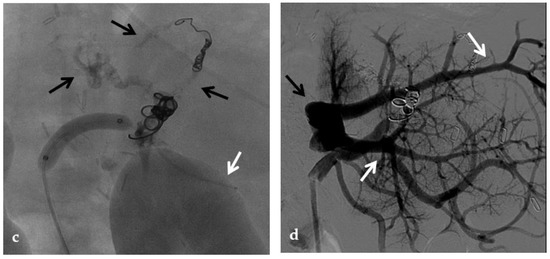

A transmesenteric approach can be used both in early PVT and in chronic PVT when transhepatic and/or transsplenic access fails. Kim et al. and Cheng et al. described the use of the transmesenteric access for portal vein revascularization and stent placement for PVT during transplantation and early PVT [83,84]. Cavalcante et al. showed that PV revascularization using a transmesenteric approach may be an alternative procedure to reestablish the portal flow to the liver graft in selected cases, being a therapeutic addition to other treatment strategies currently used to treat chronic PVT. It has acceptable technical and clinical success rates, long-term patency, and a low rate of procedure-related complications [25] (Figure 11).

Figure 11.

Anteroposterior view of a percutaneous transmesenteric portography imaging series of an acute complete portal vein thrombosis occurred early after pediatric split-liver transplantation in a 1-year-old female with biliary atresia. (a) Superior mesenteric portography performed through a surgically-placed transmesenteric sheath (white arrow) shows total occlusion of the main portal vein and its intrahepatic branches, with opacification of several portosystemic varices (black arrows). (b) Superior mesenteric portography shows effective embolization of the portosystemic shunts to reduce the flow-steal phenomenon. A mixture of N-butyl cyanoacrylate and iodized oil and metallic microcoils (arrows) were used. (c) Portography image shows angioplasty with a 5-mm non-compliant balloon catheter performed on a stiff guidewire advanced through the common portal vein (white arrow). Note the spontaneous remaining opacification caused by the mixture of N-butyl cyanoacrylate and iodized oil (black arrows). (d) Final superior mesenteric portography shows restored opacification of the portal vein anastomosis, the umbilical recess of the portal vein (black arrow) and the intrahepatic segment 2 and segment 3 branches (white arrows), with no contrast filling of the portosystemic shunts.